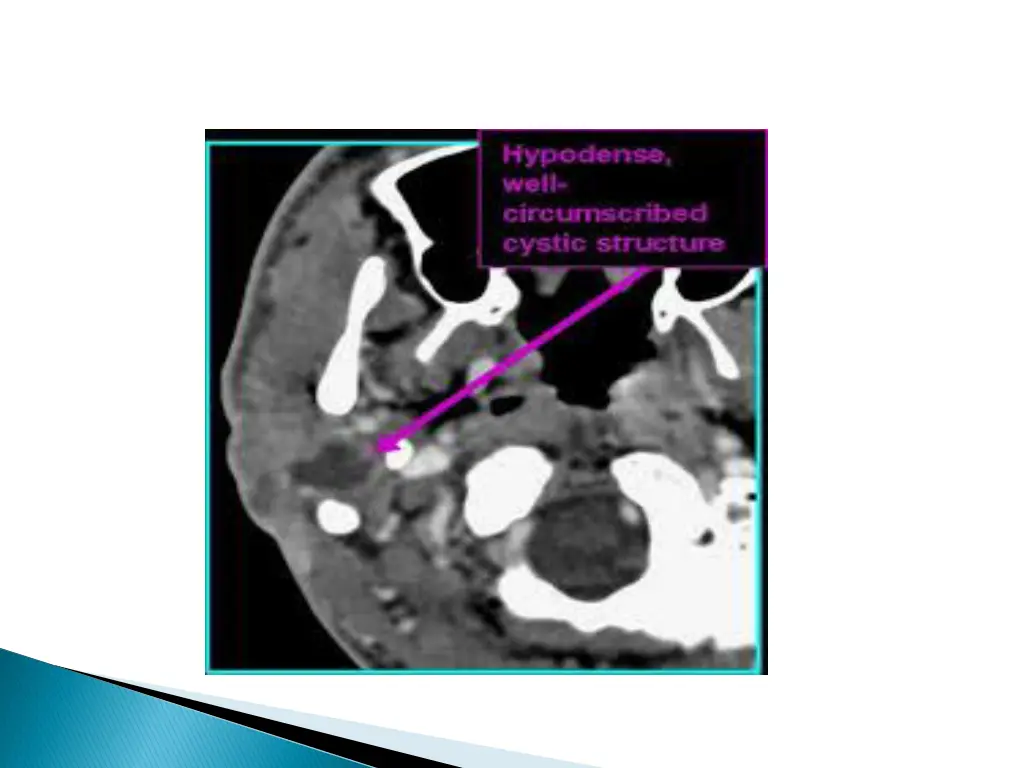

Smooth well circumscribed mass anywhere along the course of the duct. Thin walled, with peripheral rim enhancement on post contrast study. Homogenous attenuation (10-18HU). Increased attenuation suggest increased protein content and correlated with prior history of infection. Usually unilocular, occasionally septations+ Beaking of strap muscles over the surface of cyst.

CECT shows a cystic lesion in the right strap muscles.